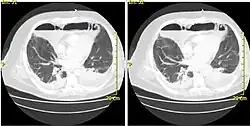

CT scan of a patient with Descending Necrotizing Mediastinitis.

Acute mediastinitis can be confirmed by contrast x-rays since most cases of acute mediastinitis are due to esophageal perforation. Other studies that can be used include endoscopic visualization, Chest CT scan with oral and intravenous contrast.

With regards to CT Imaging, the extent of involvement of the mediastinum can be evaluated. Therefore, acute mediastinitis can be classified into three categories:[9]

1. diffuse mediastinitis

2. isolated mediastinal abscess

3. mediastinitis or mediastinal abscess complicated by empyema or subphrenic abscess.